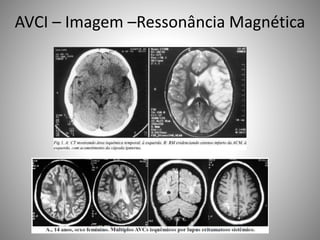

AVCI – Imagem –Ressonância Magnética

• Mais sensível para detectar isquemia precoce

• Anormalidades do tecido ou fluxo sanguíneo

• Indicadores qualitativos

• Não são capazes de predizer o volume final da

lesão ou se o dano é irrversível

• Não permitido em pacientes com dispositivos

ferromagnéticos e quase impossível em

pacientes em estado crítico